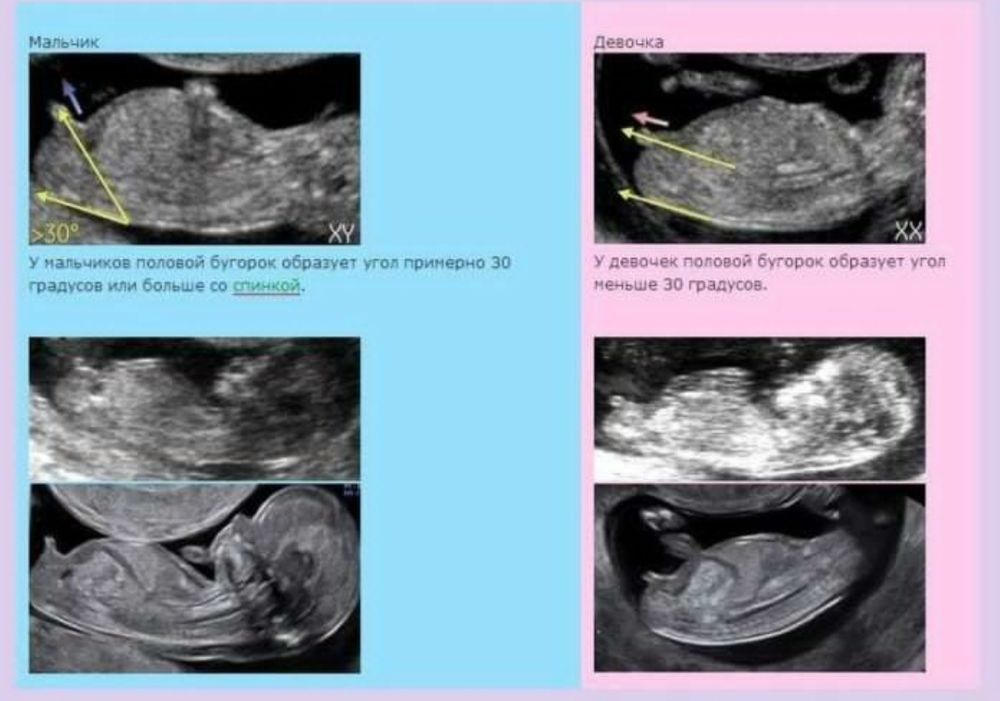

Изображение Я мало в этом понимаю, но вроде когда писюня смотрит под углом вниз вроде девочка, а если вверх, то мальчик. Там явно вниз.

Кажется девочка, если то, что я вижу - половой бугорок)